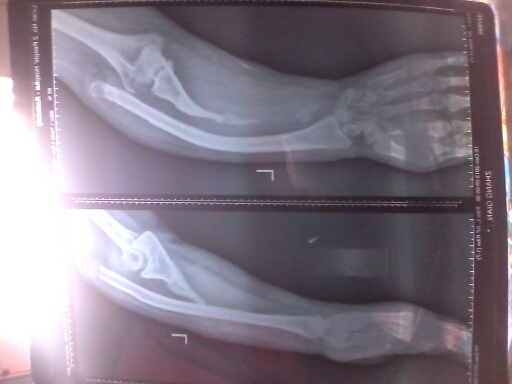

治疗先天性尺桡骨缺损,告别“单一的传统疗法”

郑州仁济医院对于先天性尺桡骨缺损的治疗,具有自己独特的疗法。率先在河南省引进伊里扎洛夫技术,延长缺损的尺桡骨。治疗不在依靠单一的传统疗法,克服了疗效不确切、恢复慢的弊端。>>>有问题直接问专家

晴晴出生后,就被发现尺骨缺损,去了很多家医院,都说不好治疗,“不仅创伤大,效果不确切,而且治疗起来非常复杂”。这样的诊断让全家人陷入了痛苦的深渊,尝试了多种疗法,让孩子遭受了很多罪,也花了不少钱,但是治疗的效果却微乎其微,成了全家人的心病。直到在网上了解了郑州仁济医院的伊里扎洛夫技术之后,经过近两个月的延长,已经基本康复。>>>点击了解康复案例

据郑州仁济医院谢书强副院长(点击咨询预约)讲,之前对于尺桡骨缺损的治疗,多是采用植骨矫形,针对于缺损比较少情况,有一定的效果,但是针对于缺损比较严重的情况,需要多次植骨矫形,病人的痛苦大、康复时间长,效果不确切。自从伊里扎洛夫骨延长技术被引进之后,对于尺桡骨缺损的治疗就变的简单、不仅康复快,而且微创、效果好。

伊里扎洛夫技术,根据尺桡骨缺损的程度,以及畸形的情况等,设计合理的延长、矫形架子,根据患处的皮肤、骨骼情况,避开神经、肌腱、血管,安装牵引架,术中出血少,甚至不出血,创伤小,术后只需观察针眼处有无感染即可。>>>点击了解技术详情